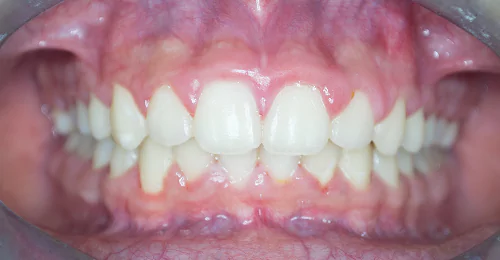

Orthodontic Case – IV

(Case Done by Dr. Sonali Deshmukh M.D.S. / Orthodontist )

Correction of Open Bite

Pre Treatment